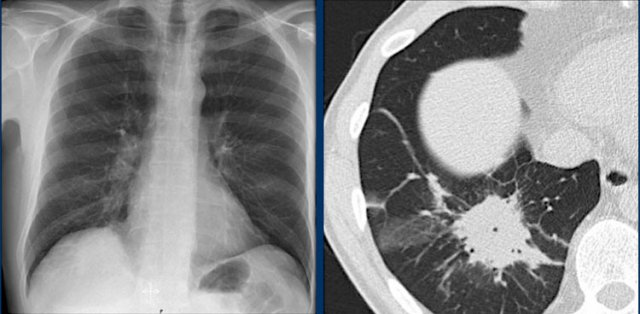

Hili

The normal hilar shadow on chest radiography is predominantly vascular in nature—comprising approximately 99% of pulmonary arteries and, to a lesser extent, pulmonary veins (1).

These vascular structures have well-defined, smooth margins and demonstrate normal branching patterns.

An important anatomical consideration is that the left hilum is normally situated higher than the right.

This relationship arises from the course of the pulmonary arteries: the left pulmonary artery arches over the left main bronchus, while the right pulmonary artery courses anterior to the right main bronchus, which is typically positioned lower than its left counterpart.

In a minority of cases, the hila may be at the same level, but the right hilum should never be higher than the left.

In this illustration, lower lobe pulmonary arteries are colored blue to indicate deoxygenated blood.

These arteries have a more vertical orientation compared to the pulmonary veins, which run more horizontally toward the left atrium, located inferior to the level of the main pulmonary arteries.

On lateral chest radiographs, both pulmonary arteries and veins are identifiable and should not be misinterpreted as lymphadenopathy. Occasionally, pulmonary veins may appear prominent.

The left main pulmonary artery passes superior to the left main bronchus and lies higher than the right pulmonary artery, which courses anterior to the right main bronchus.

The included images are thick-slab sagittal CT reconstructions of the thorax, which enhance visualization of hilar structures.

The lower lobe pulmonary arteries descend from the hilum in a vertically oriented fashion.

Radiographically, these vessels are colloquially referred to as the “little finger” due to their size and shape, approximating that of a little finger (1).

On PA chest radiographs, the "little finger" of the right lower lobe pulmonary artery is visible in approximately 94% of normal individuals, while on the left side it is visible in about 62% (1).